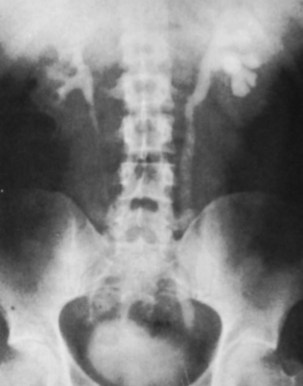

The majority of cases will show positive findings on excretory urography, the most common findings being hydrocalycosis, hydronephrosis, or hydroureter due to stricture formation (Wang et al, 2003). Early signs include the moth-eaten appearance of calyceal erosion and papillary irregularity. These signs are best seen on early excretory films, because they are often masked by increasing density of the contrast on later films of the IVU. Cavitary lesions communicating with the collecting system are characteristic of TB. These lesions eventually enlarge as parenchymal destruction ensues, and a picture similar to chronic pyelonephritis may be seen. Fibrotic distortion of the collecting system and ureter is also seen. Calyceal obliteration and amputation, hydrocalycosis, segmental or total hydronephrosis, and a shriveled reduced-capacity renal pelvis may all be signs of renal tuberculosis (Figs. 16-2 and 16-3). Scarring and angulation of the ureteropelvic junction (UPJ) may also occur, the so-called “Kerr’s kink” (Matos et al, 2005). Ultimately diminished or absent function and extensive calcification may be seen with autonephrectomy. If nonvisualized on IVU, the kidney is best evaluated by computed tomography (CT) or ultrasonography.

Tuberculosis of the ureter is commonly seen as a rigid, straightened “pipe-stem” ureter. A beaded, corkscrew appearance is sometimes also seen. Ureterovesical junction obstruction is caused by tuberculous cystitis or strictures of the distal third of the ureter (Fig. 16–4). Secondary stone formation on top of this stricture is an occasional finding. The cystogram films may show a small contracted bladder due to excessive fibrosis (Fig. 16–5). Of note, although IVU is being phased out by CT-urography in many developed countries (Stacul et al, 2008), IVU continues to be a reliable imaging modality for genitourinary TB in most parts of the world.